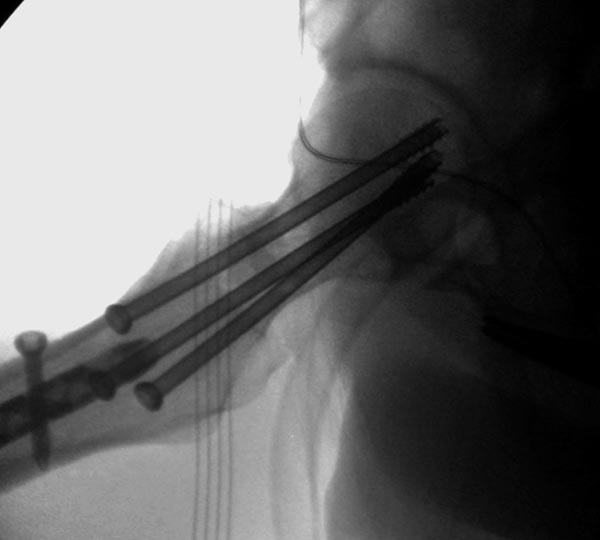

Пока надо делать снимки в классических укладках, т.е. хотя бы в двух проекциях. А по тактике из всех переломов: шейка является приоритетным и ургентным. Идеально фиксировать канюлированными винтами, но усложняется тем, что имеется перелом верхушки вертела. Навряд ли получится закрыто, надо открывать. Все зависит от возможностей на месте (писали насчет DHS), можно и интрамедуллярный гвоздь, но не надо укорачивать, только пустить overlapping, т.е. пластина от DHS покрывает часть гвоздя.

Здесь выставлен ренгенограммы больного, ему 21, травму получил в результате высокоскоростной погони на украденной машине, которая закончилась смертью трех остальных “боевых комрадов”. Начатую коллегой открытую операцию на шейке пришлось закончить мне, установкой винтов и ретроградной фиксацией бедра. Выписка в обычное сроки и наблюдался амбулаторно. Каждый раз напоминали о возможности осложнений ввиде несращения! По истечению 4 месяцев появились признаки варусной деформации. На СТ срезах несращение шейки и бедра. Риминг, замена на более толстый гвоздь и вальгусная остеотомия.